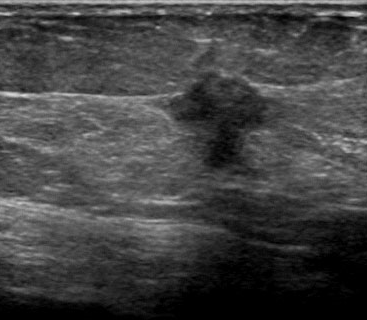

The target dataset was developed from 35 breast ultrasound scans that were segmented by an image-processing expert with extensive experience in breast lesion segmentation (the second author). The images, collected from the Web, are of different dimensions, ranging from to pixels (Figure 3, images resized for sake of illustration). These are the same images used to introduce EFIS originally [1].

Ultrasound images are generally difficult to segment, primarily due to the presence of speckle noise and low level of local contrast. It should be noted that the segmentation of ultrasound actually does require a complete processing chain, (including proper preprocessing and post-processing steps). However, the purpose of using these images was solely to demonstrate that the accuracy of the segmentation can be increased with the application of SC-EFIS.